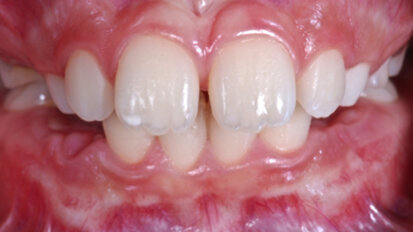

Rehabilitace Straumann